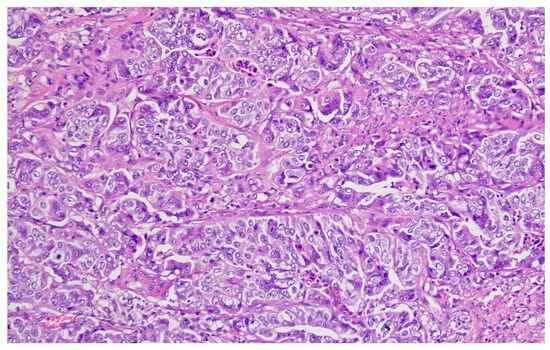

Hematoxylin–eosin staining was used for the direct exposure of the histopathologic subtypes (according to the WHO classification) present in the studied group, as shown in optical microscopy images.

Representative histopathological images of different tumor types are shown in Figure 2, Figure 3, Figure 4, Figure 5, Figure 6 and Figure 7, illustrating the histological subtypes observed in our cohort.

Figure 6. Poorly differentiated (G3) adenocarcinoma showing solid growth pattern with high nuclear pleomorphism and increased mitotic activity (H&E, ×200, scale bar = 100 μm).